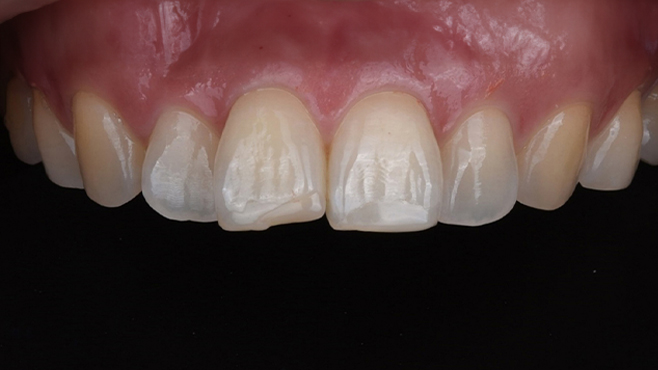

맞는 건 괜찮은데… 충치는 못 참겠습니다|20대 격투기 선수 치과 방문기